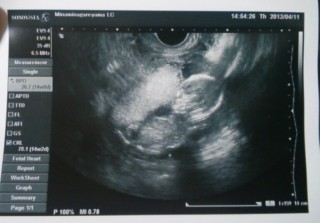

心臓も元気に動いており、順調に育っていました♪

4週間ぶりの検診☆

CRL(T)97.3mm